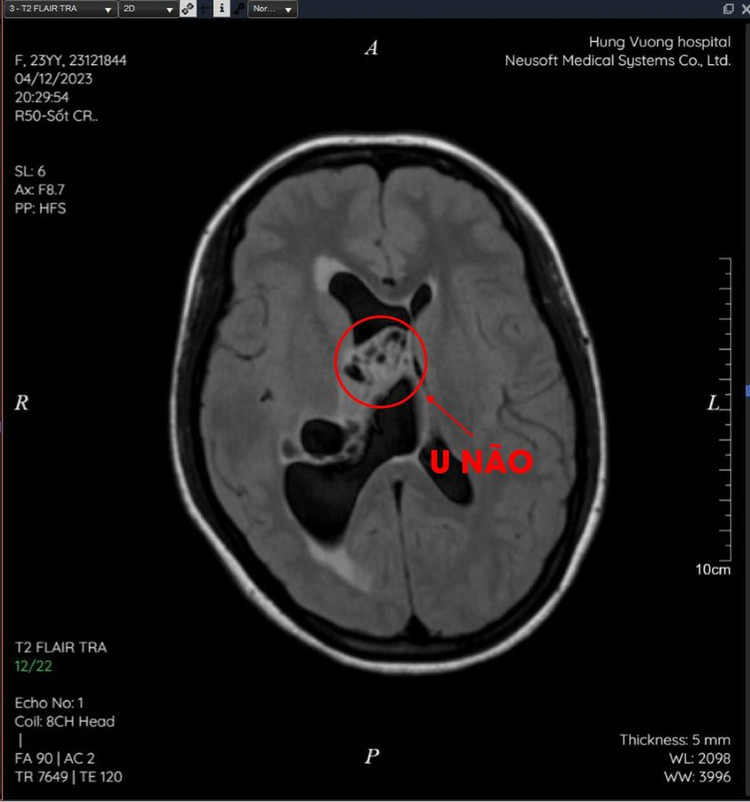

Sau khi được chụp cộng hưởng từ và tiến hành hội chẩn với ý kiến các chuyên gia đầu ngành, các bác sĩ tại Khoa Chẩn đoán hình ảnh - BVĐK Hùng Vương kết luận: U đám rối mạch mạc não thất bên bên phải xâm lấn hồi hải mã phải.

| Khối u não trên phim chụp |